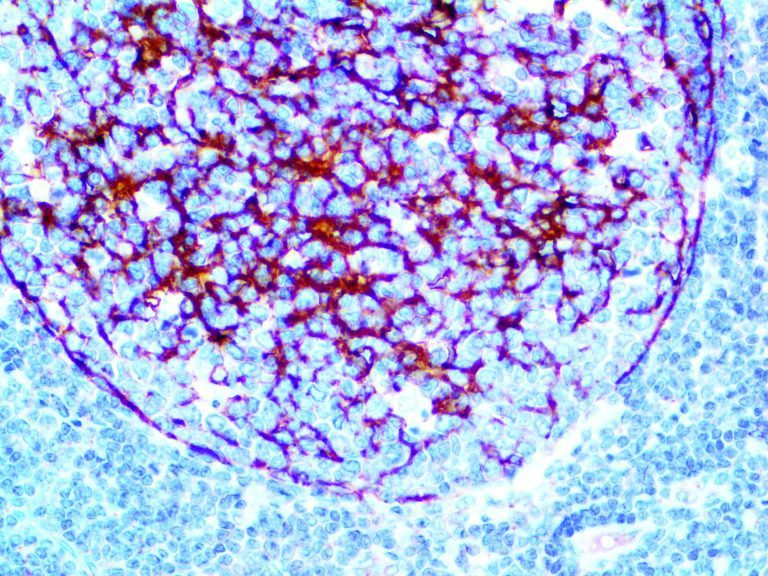

The first cytokines released are interleukin 1β (IL-1β) and tumor necrosis factor-α (TNF-α), which attract a variety of circulating white blood cells (WBCs) to the infection site, including neutrophils, monocytes, macrophages, and natural killer (NK) cells. This response, along with the antipathogenic chemicals released by these cells (i.e., complement), comprise the innate immune response. These cells directly attack the invading pathogen and also release additional cytokines, chief among them interleukin-1 and 6 (IL-6). IL-6 is essential for invoking the adaptive immune response, which calls T-cells, B-cells, and T helper (Th) cells to the infection site. IL-6 also stimulates further recruitment, proliferation and activation of macrophages.

It is the ICU physician who is most likely to witness one of the deadliest manifestations of the abnormal immunological response, the cytokine storm syndrome (CSS). This response is also referred to by some as the cytokine release syndrome (CRS). CSS is characterized by continuous activation and expansion of macrophage and lymphocyte populations, which secrete large amounts of cytokines, causing the cytokine storm. This massive cytokine release is akin to hemophagocytic lymphohistiocytosis (HLH) disease, a syndrome characterized by initial unchecked and persistent activation of cytotoxic T lymphocytes and NK cells.